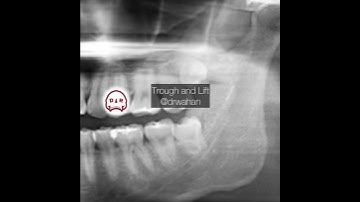

Mesioangular Wisdom Tooth Extraction with Voiceover Black + White